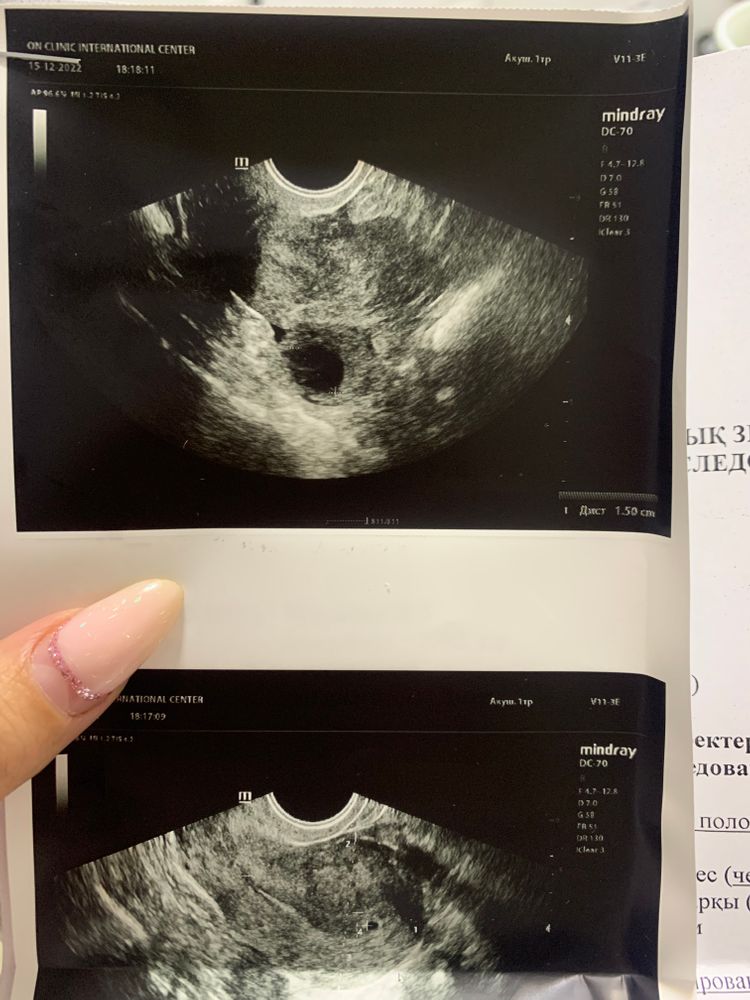

Мамочка в Зачатие 3 года Наша бусинка ❤️ Фолликулометрия Не выдержали до 30 🤣. Поставили срок 4 недели. Посмотрите еще 20 записей на эту тему Отменить Ответить Эмми А как вы поняли, что ждёте дочку?) 26.12.2022 Ответить Мамочка Эмми, никак)) просто на удачу 😃 26.12.2022 Ответить Эмми Мамочка, после двух девочек вы хотите ещё одну? 😳😃 26.12.2022 Ответить Мамочка Эмми, да хотим еще дочку) 26.12.2022 Ответить Karolina Bel Как бы мне еще неделю выдержать до первого узи. 😔 15.12.2022 Ответить Наталья Какое у Вас красиво ПЯ. Лёгкой беременности!-) 15.12.2022 Ответить Мамочка Наталья, спасибо ❤️ 15.12.2022 Ответить расшифровка узи Сос. Нет доминантного фолликула. Но есть жидкость Чаты Беременных Выберите чат: Январята-2026 Февралята-2026 Мартята-2026 Апрелята-2026 Майчата-2026 Июнята-2026 Июлята-2026 Августята-2026